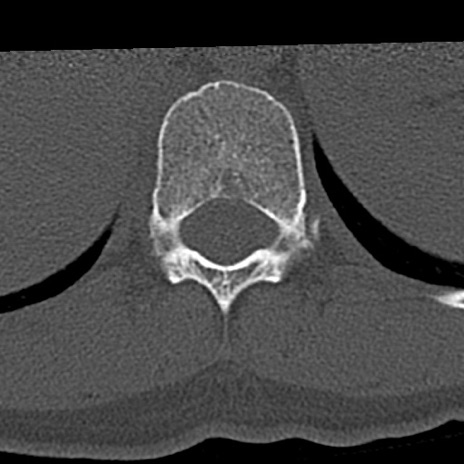

腰椎CT

横断像と矢状断像